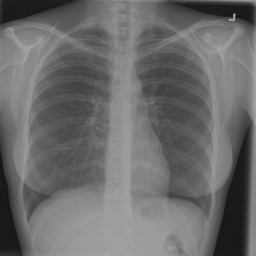

Anomaly detection is the problem of recognizing abnormal inputs based on the seen examples of normal data. Despite recent advances of deep learning in recognizing image anomalies, these methods still prove incapable of handling complex medical images, such as barely visible abnormalities in chest X-rays and metastases in lymph nodes. To address this problem, we introduce a new powerful method of image anomaly detection. It relies on the classical autoencoder approach with a re-designed training pipeline to handle high-resolution, complex images and a robust way of computing an image abnormality score. We revisit the very problem statement of fully unsupervised anomaly detection, where no abnormal examples at all are provided during the model setup. We propose to relax this unrealistic assumption by using a very small number of anomalies of confined variability merely to initiate the search of hyperparameters of the model. We evaluate our solution on natural image datasets with a known benchmark, as well as on two medical datasets containing radiology and digital pathology images. The proposed approach suggests a new strong baseline for image anomaly detection and outperforms state-of-the-art approaches in complex medical image analysis tasks.